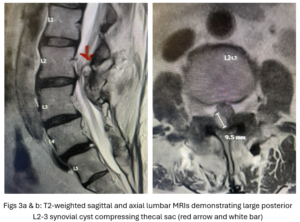

This 54-year-old female with a long history of low back pain presents with three weeks of a progressive right footdrop with associated numbness and tingling of the right leg. In addition, she had right lateral hip pain down to the dorsum of her foot. She first noticed her right foot slapping the floor when she walked. She had no prior trauma or unusual activity before this began. Her chiropractor, who had treated her back pain for a long time, first noticed the foot drop and referred her for further evaluation. She presented with ⅖ strength in her right dorsiflexor. MRI revealed a large right L4-5 foraminal synovial cyst with some mass-effect on the thecal sac. (Fig. 1) She also had an associated grade 1 spondylolisthesis. Because the cyst was more foraminally-oriented, it had the majority of its effect on the right L4 nerve root. It was felt the patient required surgery to attempt to reverse her weakness. We performed a decompressive laminectomy at L4, removing the inferior facet process on the right in order to gain lateral and foraminal access to the right L4 nerve root. In the lateral recess there was a heap of inflammatory tissue which we entered, revealing the cyst. The medial wall was stuck to the dura. We internally decompressed the cyst which was mainly gelatinous material with some fluid. We dissected and removed as much of the cyst we could safely remove but left the medial wall for fear of removing it would cause a CSF leak, upon removing the bulk of the cyst we encountered anteriorly the descending and exiting right L4 nerve root which was purplish in color and clearly inflamed. We performed a generous foraminotomy of the right L4 as well as the right L5 nerve root. We also performed an instrumented fusion at L4-5 (Fig. 2).

This 50-year-old female with a long history of low back pain and a prior history of multiple lumbar surgeries with instrumentation. She had a L3-5 laminectomy with instrumentation about 7 years prior and now presents with progressive worsening of low back pain. The pain was worse with activity, standing, walking, and prolonged sitting. She had an MRI which showed next segment degeneration at L2-3 with stenosis and the development of a large posteriorly-oriented synovial cyst with thecal sac compression (Fig. 3). The patient failed all means of conservative management including physical therapy and epidurals. We decided to perform an L revision laminectomy to decompress and remove the cyst as well as explore her prior fusion. In this case, again the anterior wall of the sac was completely stuck to the dural membrane. Therefore, we internally decompressed the cyst which was mainly degenerated, necrotic material and removed as much wall of the cyst that could be safely removed. There was some fluid within the cyst. Of note during the dissection of these cysts there is often a release of cyst fluid the patient was well-decompressed. We removed the prior instrumentation and added a new L2-3 construct (Fig. 4). The patient had an uneventful hospital course and was discharged on post op day 2.